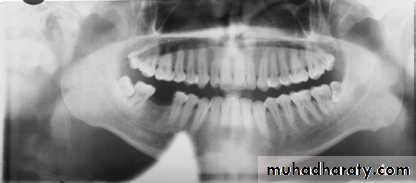

In a good panoramic radiograph:

The mandible is “U” shaped.The condyles are positioned about equal distance from the inside edges of the image and 1⁄3 of the way down from the top edge of the image.

The occlusal plane exhibits a slight curve or “smile line,” upwards.

The roots of the maxillary and mandibular anterior teeth are readily visible with minimal distortion.

Magnification is equal on both sides of the midline.

1, Mandibular condyle. 2, Articular eminence. 3, Coronoid process of mandible superimposed on zygomatic arch. 4, Posterior wall of maxillary sinus. 5, Posterior wall of zygomatic process of maxilla. 6, Hard palate. 7, Nasal septum. 8, Tip of nose. 9, Dorsum of tongue. 10, Hyoid superimposed over inferior border of mandible. 11, Inferior border of maxillary sinus. 12, Image of cervical spine. 13, Medial border of maxillary sinus. 14, Infraorbital canal. 15, Infraorbital rim. 16, Pterygomaxillary fissure. 17, Anterior border of the pterygoid plates. 18, Lateral pterygoid plate superimposed over soft palate and coronoid process of mandible. 19, Ear lobe. 20, Inferior border of mandibular canal. 21, Mental foramen. 22, Posterior wall of nasopharynx. 23, Inferior border of mandible superimposed from opposite side. 24, Soft palate over mandibular foramen of mandible.